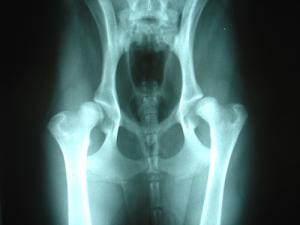

Bilateral_hip_dysplasiaCanine Hip dysplasia is the abnormal development of the head of the femur. Instead of fitting properly in the socket of the hip joint, the femur fits loosely. Because of the bulldog’s unique skeletal structure and stature, they can often be misdiagnosed with hip dysplasia. Bulldogs naturally have shallow hip and joint sockets. However, in the case of bulldogs their unique muscular structure has adapted to support the hip in a way that is not seen in other breeds.….Mother Nature’s own compensation for the uniqueness of Bulldogs. For more info on Bulldog Hip Dysplasia visit the Orthopedic Foundation For Animals